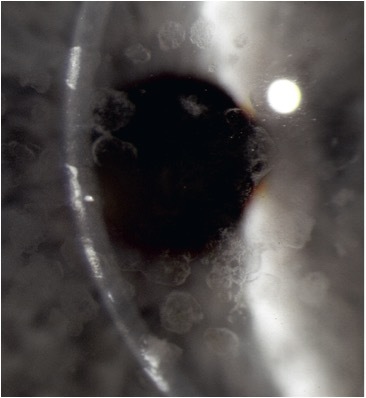

what is granular dystrophy?

*earliest seen dystrophy - in first decade VA reduction > 40 y/o centrally discrete focal white deposits all stromal depths “cornflakes”, area between lesions is clear (deposits are hyaline-like material) RCE is rare